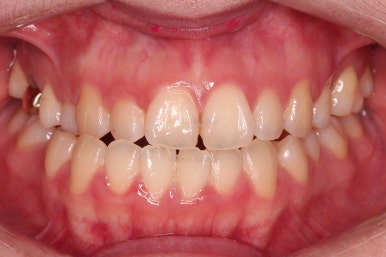

초진 시, 입안의 모습입니다.

아래 중앙선이 윗니의 정중선에 비해 우측으로 많이 쏠려있고요.

전반적으로 아래 치열이 우측으로 가 있어서 특히 송곳니 부분에서의 반대교합이 두드러졌어요.

(아래 송곳니가 위 송곳니보다 밖에 나와있는 상태)